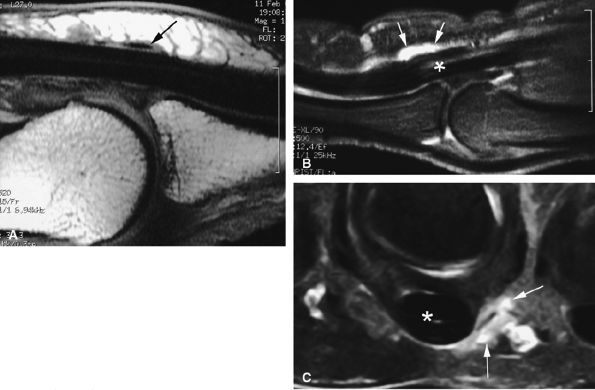

|

FIGURE 11.61 ● Hypothenar hammer syndrome. (A) MR angiography shows a typical corkscrew pattern (arrows) of the ulnar artery extending to the deep palmar arterial arch. (B) Axial post-contrast fat-suppressed T1-weighted image depicting inflammatory thickening of the ulnar artery walls (arrows).